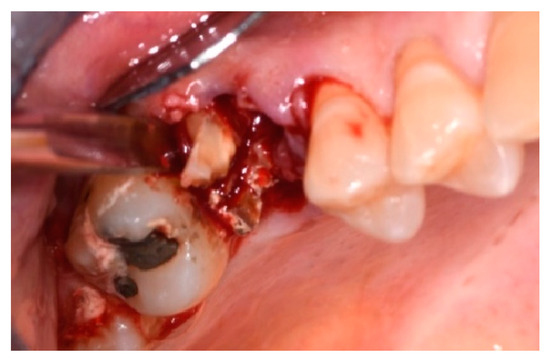

2.4. Surgical Procedure, Evaluation at Follow-Up, and Collection of Radiographic Data

- Use of Magnetic Mallet® inserts only and code of the insert(s) used;

- Use of Magnetic Mallet® inserts and extraction pliers only;

- Use of inserts, pliers, and hand levers;